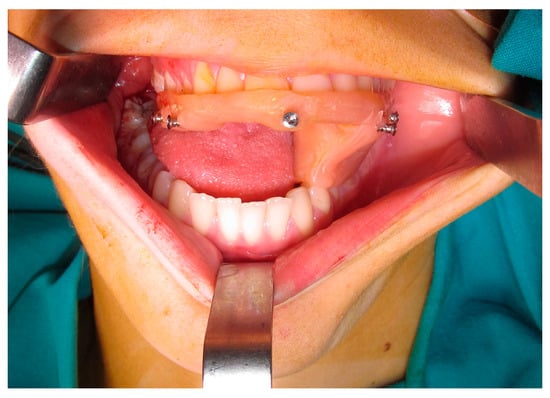

| Case 2 Impacted teeth in Pfeiffer Syndrome | 0.5 mm | 0.3 mm | 0.6 mm | |

| Case 3 Impacted teeth in Apert Syndrome | 0.3 mm | 0.5 mm | 0.4 mm | 0.5 mm |

| Case 4 Impacted teeth | 0.3 mm | 0.2 mm |